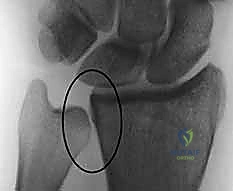

- الأشعة السينية (X-rays):

هي الخطوة الأولى لتقييم الكسر. يتم أخذ صور من زوايا متعددة (أمامية خلفية، جانبية، ومائلة) لتحديد موقع الكسر الأساسي ودرجة الانزياح والتقصير في عظم الكعبرة.